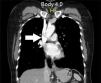

Mujer de 53 años, sin antecedentes de importancia, quien ingresa a urgencias por 2 días de hematemesis sin dolor abdominal; en el examen físico se registra una frecuencia cardíaca de 90 con presión arterial de 100/60 y tacto rectal positivo para melenas. Fue llevada a endoscopia, donde se observa una unión gastroesofágica sin alteraciones (fig. 1) y 2 dilataciones venosas en el tercio proximal del esófago, sin evidencia del sangrado activo (fig. 2), indicativo de cuadro de varices en Downhill, por lo que se realizó tomografía computarizada de tórax que mostró imagen de trombo en vena cava superior (fig. 3). Se inició manejo con anticoagulación con enoxaparina, con posterior control endoscópico a las 72h, el cual mostró disminución del tamaño de las varices esofágicas. Se iniciaron estudios de hipercoagulabilidad, los cuales fueron normales a excepción de la mutación de factor V de Leiden.